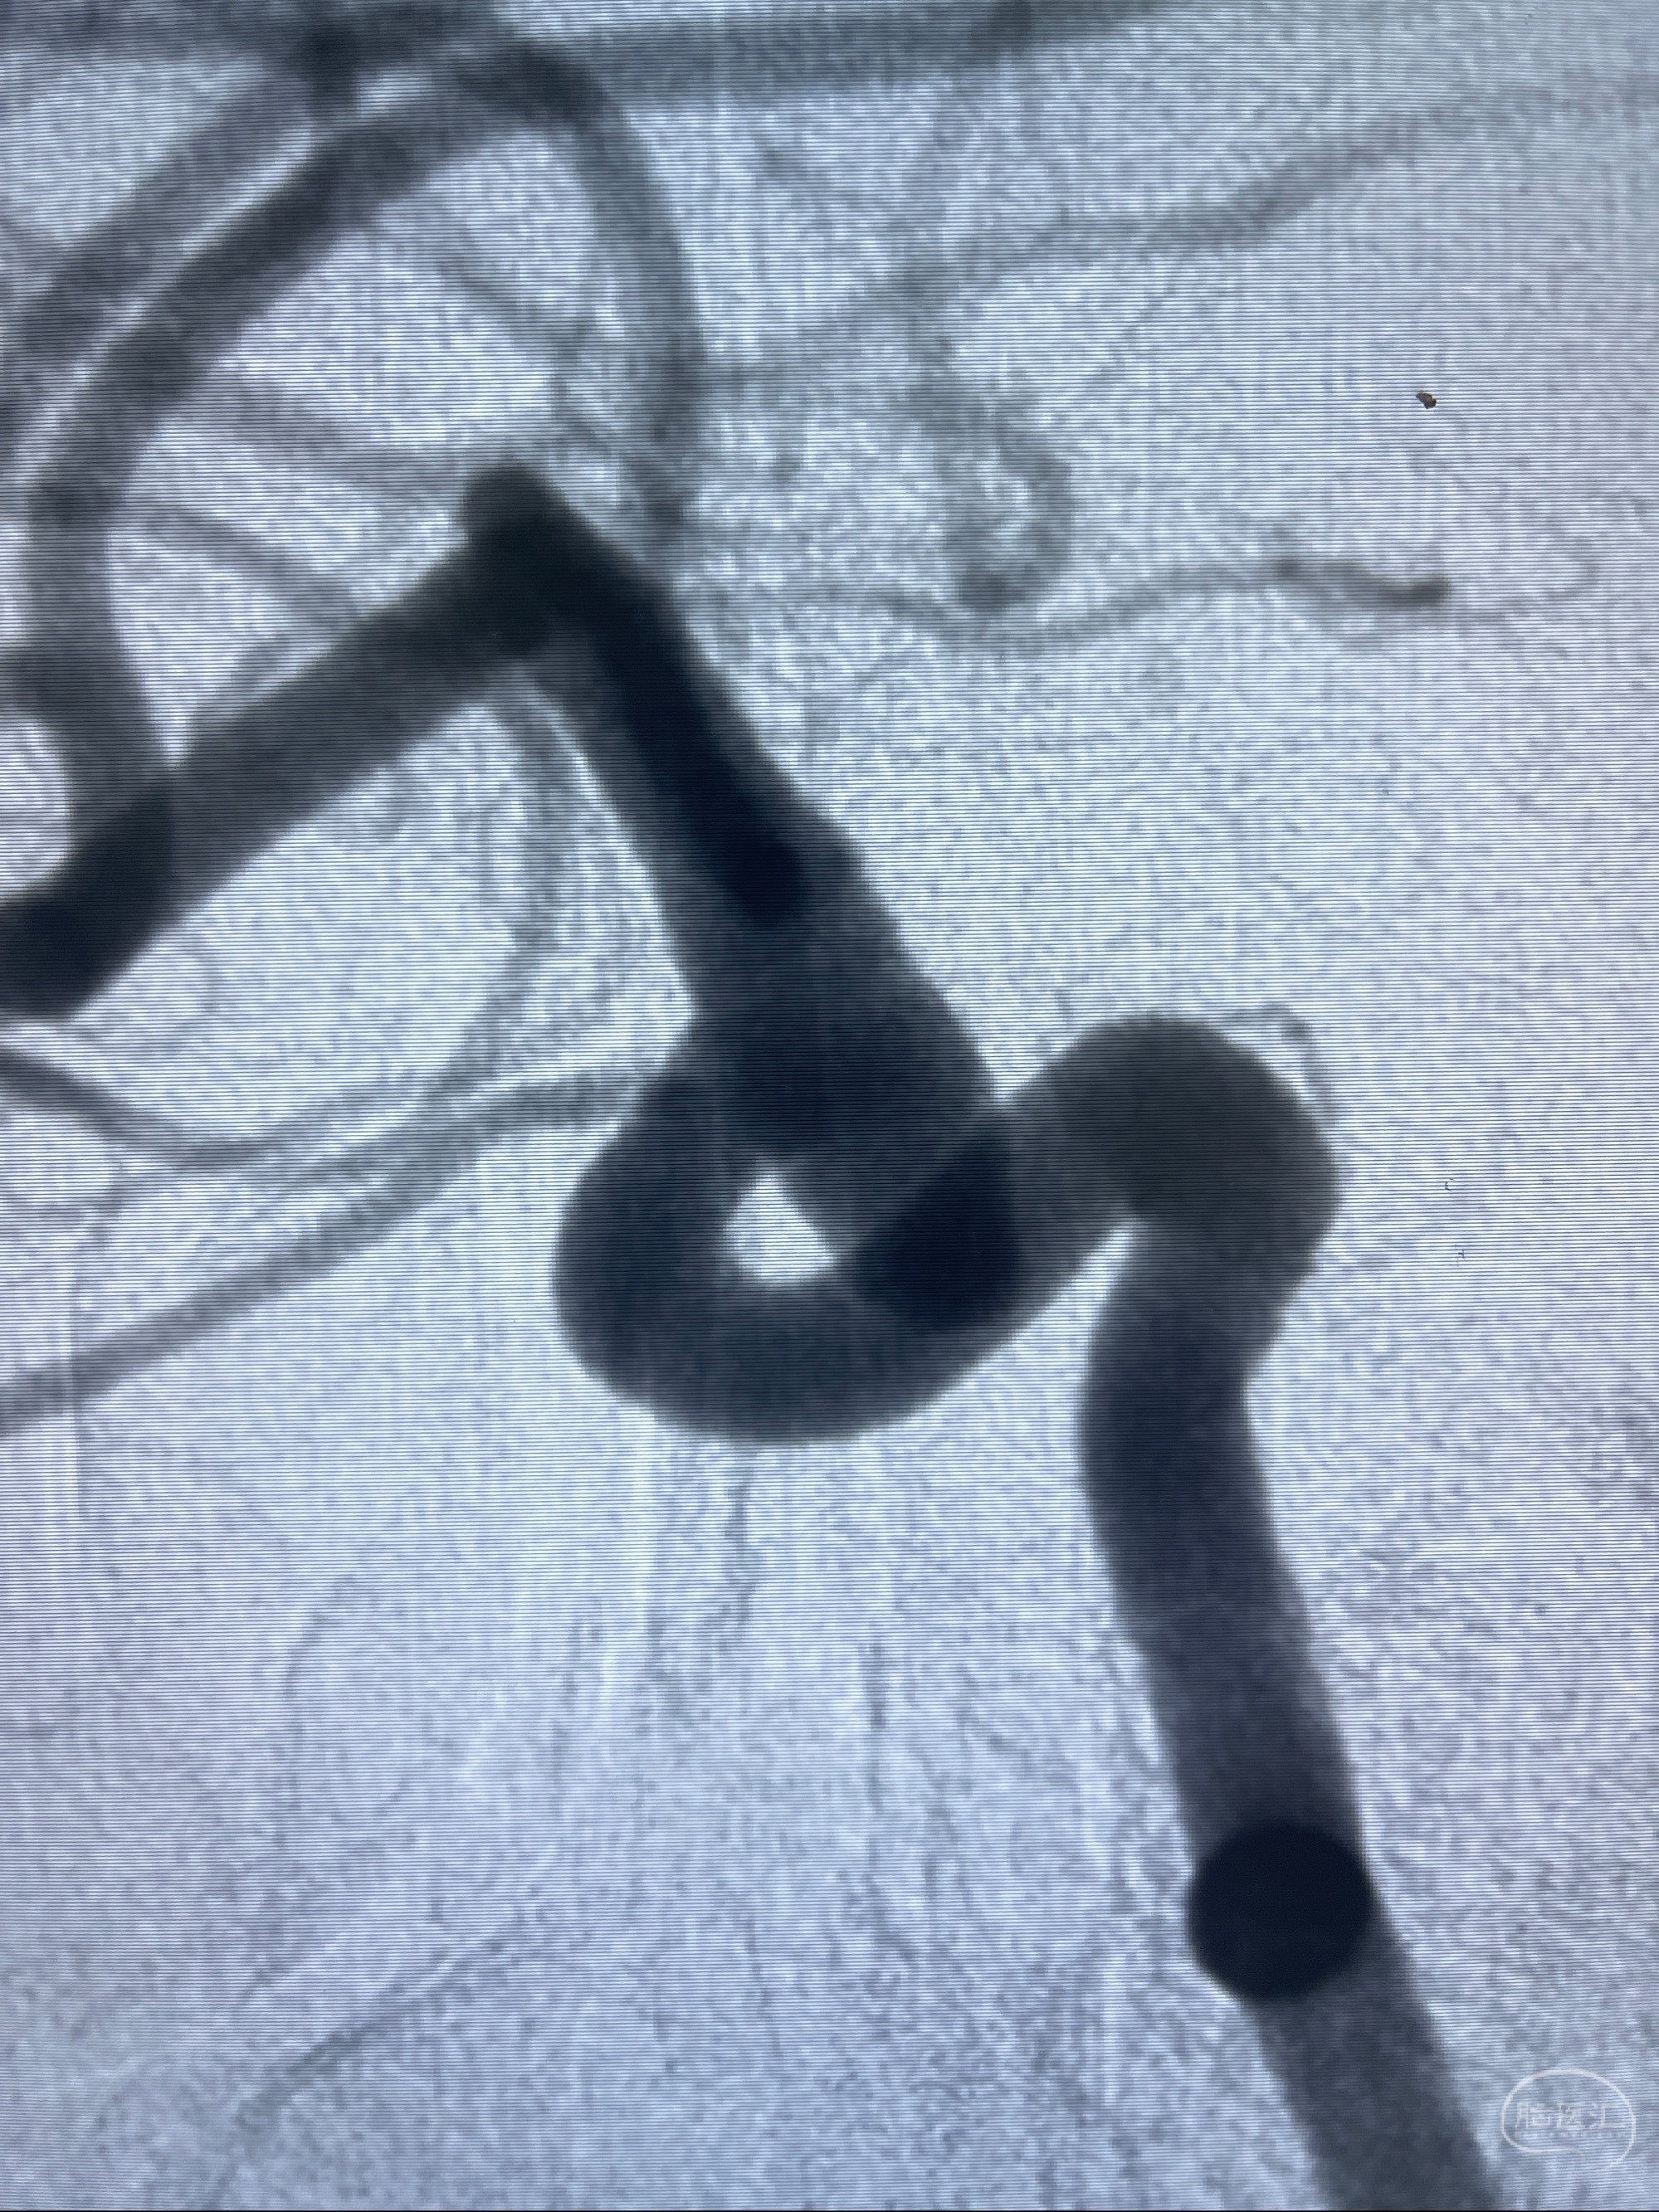

1.右侧颈内动脉眼动脉段动脉瘤

2023-07-27全脑血管造影:双侧颈内动脉眼动脉段动脉瘤,右侧较大

2023-08-01全麻下行双侧颈眼动脉瘤支架辅助栓塞

- pipeling4.5-20mm

- pipeline 4.0-20mm